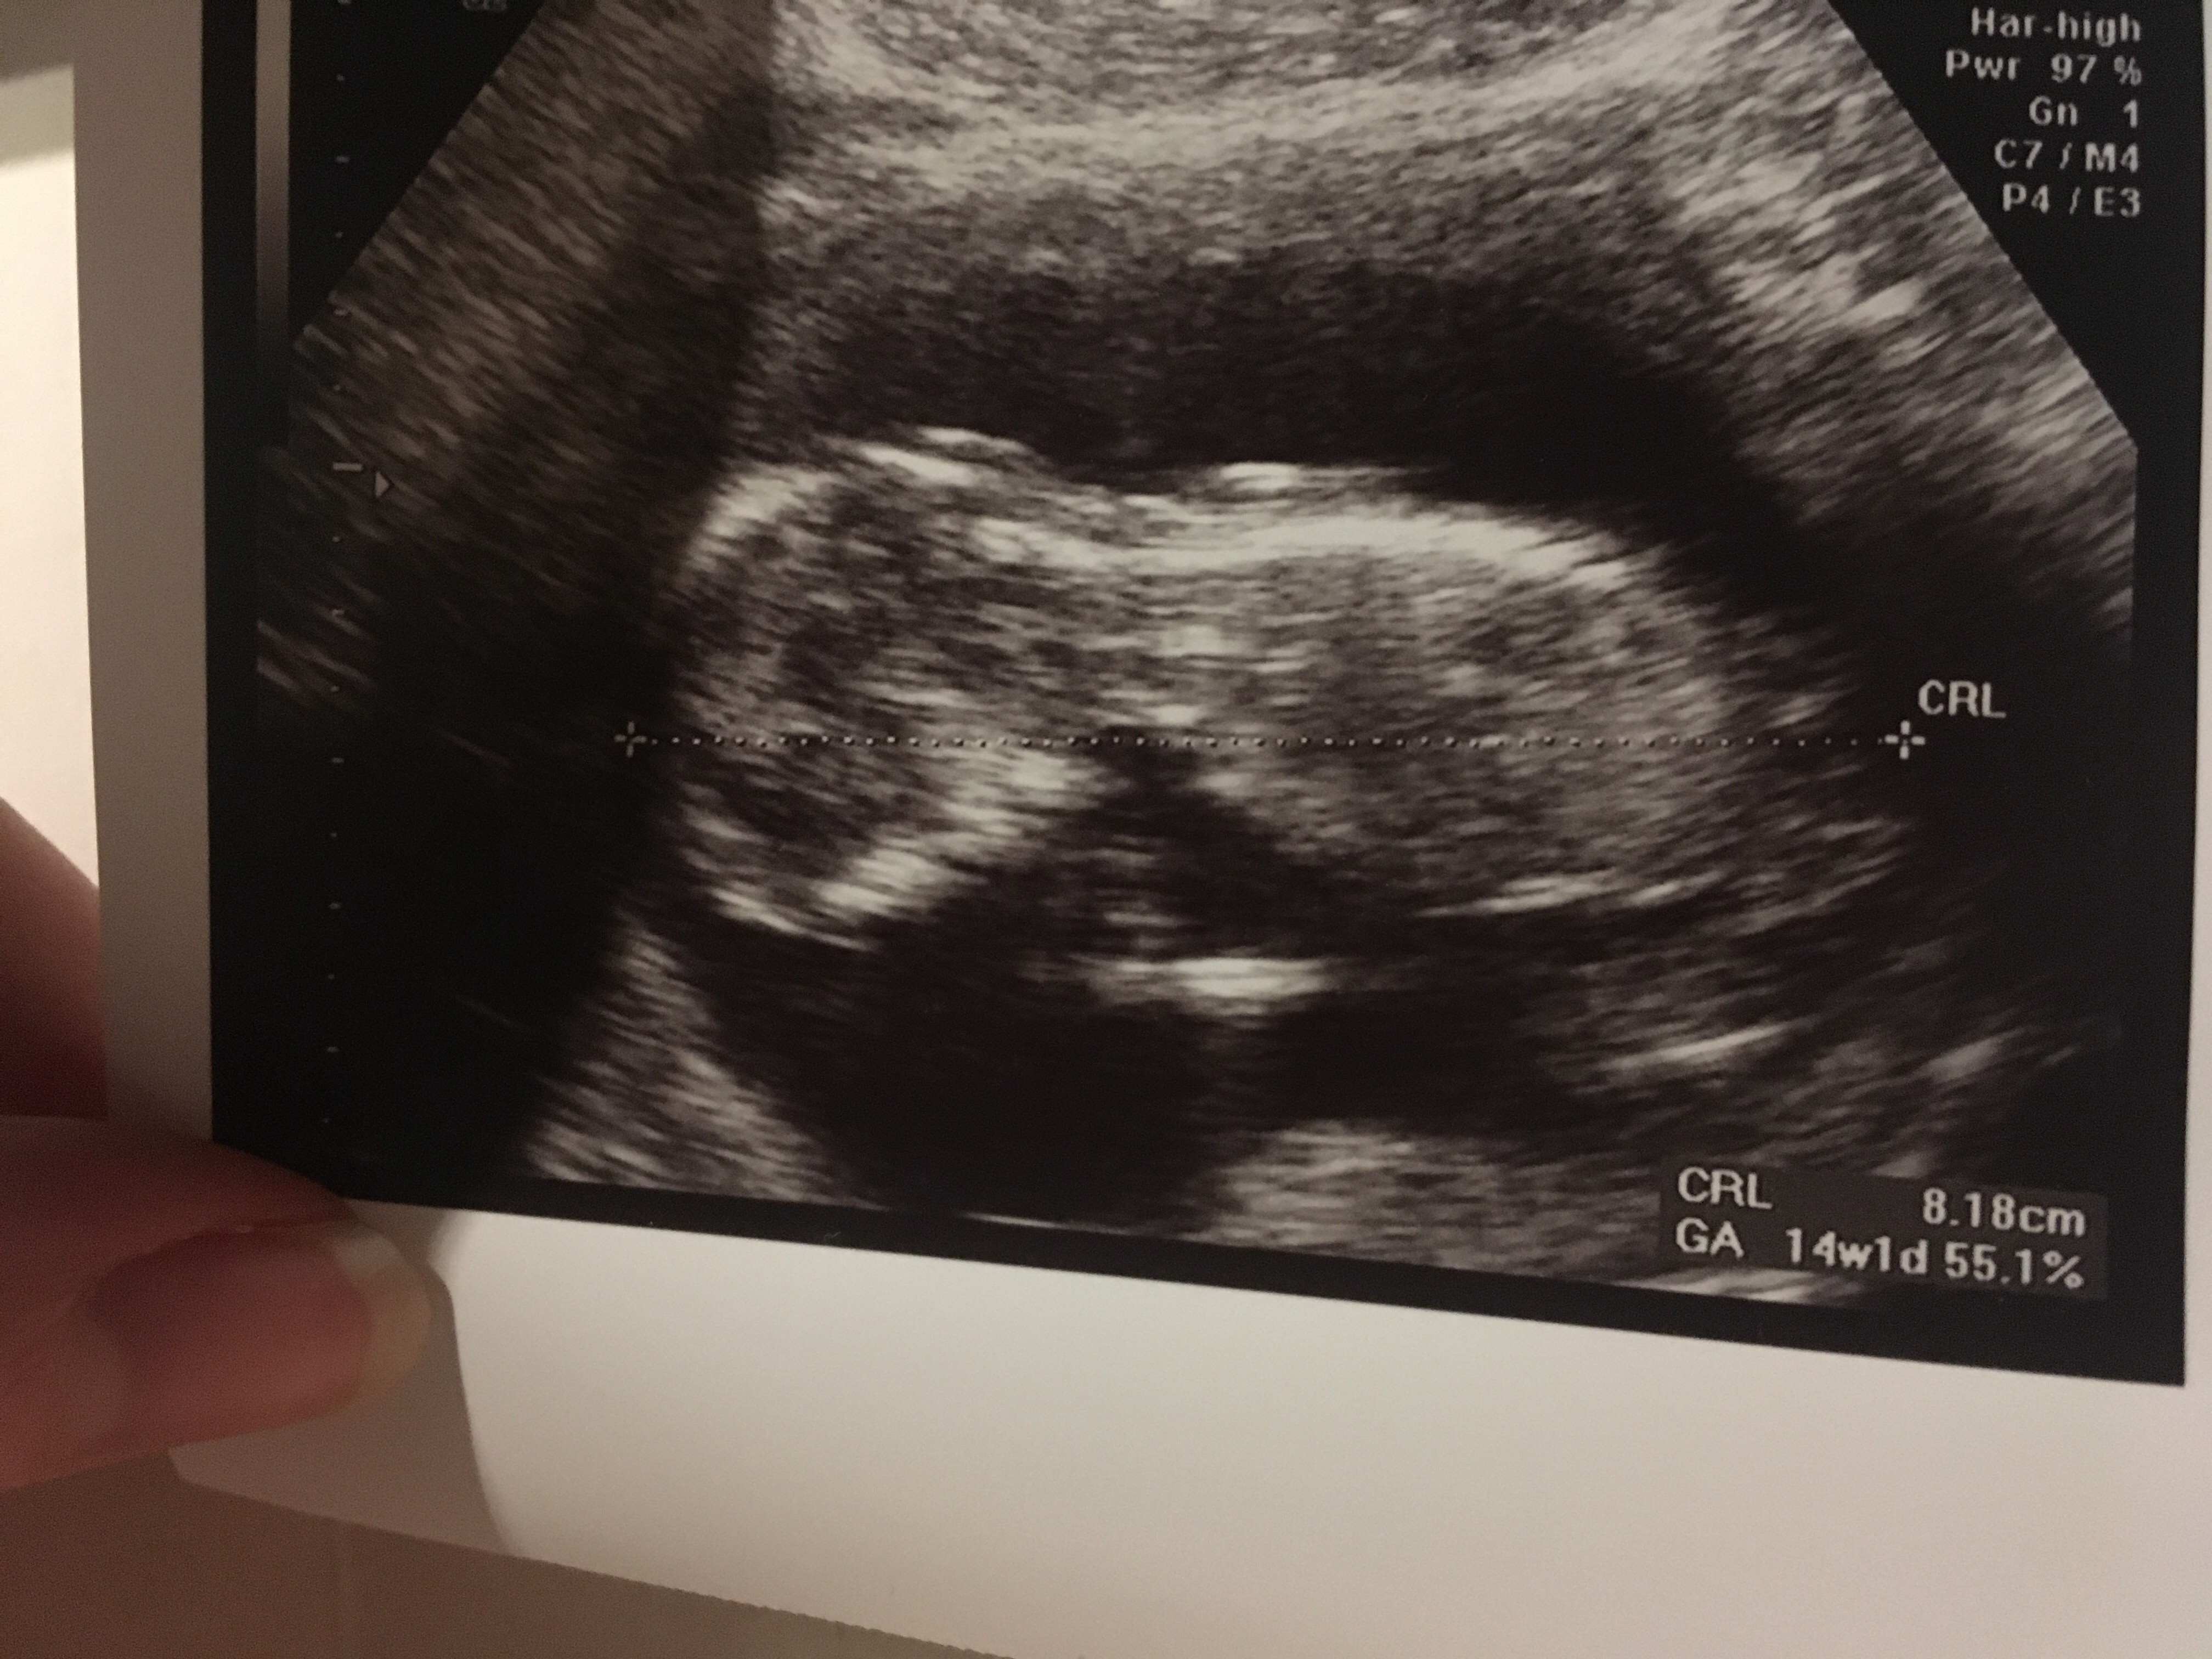

My dzisiaj po usg prenatalnym i wyszło ok teraz czekamy na wyniki z krwi i całościowe omówienie badań. Mimo, że to moja pierwsza wizyta na NFZ - muszę przyznać, że jestem zachwycona. Super atmosfera, wszyscy bardzo mili, badanie trwało z pół godziny, lekarz sam wszystko tłumaczył, zdjęć dostałam chyba z 10...kilka razy tak mnie rozśmieszył, że widziałam jak maluszek od tego śmiechu podskakuje Co do ilości usg to pewnie trochę przesadzam bo i na lux med chodzę i prywatnie raz w miesiącu ... dlatego też podpytałam o to moją lekarkę i ona mówi, że samo usg to nie ma problemu ale nie przesadzałaby z zbyt częstym sprawdzaniem serduszka (nie wiem czy tylko o tętno chodzi czy coś więcej) ...

Załączniki

• image.jpg

image.jpg

1,8 MB · Wyświetleń: 105